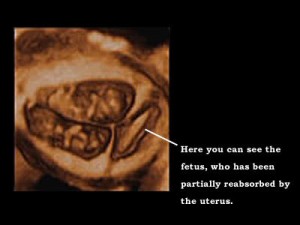

ฝาแฝดในท้องเด็กผู้หญิง (She Ain’t Heavy, She’s My Partially Absorbed Embryonic Twin)

เด็กหญิงกรีกไปหาหมอเพราะปวดท้อง ซึ่งหมอแปลกใจเมื่อพบว่าท้องของเธอบวมโต เพราะมีฝาแฝดที่เกิดจากไข่ใบเดียวกันอยู่ในท้อง แต่ผ่าออกได้โดยปลอดภัย อาการนี้ซึ่งเรียกว่า “Vanishing Twin Syndrome” (โรคแฝดที่สูญหาย) ไม่ใช่ไม่เคยมี ผู้เชี่ยวชาญบอกว่ามีบ่อย ถึง 1 ต่อ 8 ของการตั้งท้อง แต่ส่วนใหญ่แฝดจะซ่อนอยู่ในตัวคู่แฝด หรือในตัวมารดาชนิดมองไม่เห็น สำหรับกรณีนี้ ตัวอ่อนขนาด 2 นิ้ว ในท้องของเด็กหญิงไม่มีสมอง แต่มีผมและตา